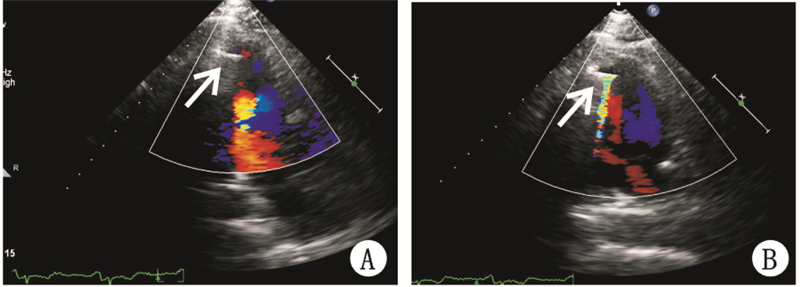

经胸超声心动图监测3例患者中2例伞叶足位于左心尖,指引导管和心脏长轴一致。1例伞叶足靠近左室下壁中下段(图 1A),在经胸超声心动图直视下进行及时调整后指引导管和心脏长轴保持一致(图 1B)。术中猪尾导管造影及超声心动图监测均提示封堵器位置固定良好。2例左心声学造影于左室显影即刻未发现室壁瘤内造影剂信号(图 2A),彩色多普勒检查未探及伞周血流;1例左心声学造影于左室显影即刻室壁瘤内可见少许造影剂信号(图 2B),彩色多普勒检查探及伞周少许残余血流信号(图 3A)。3例彩色多普勒检查Parachute伞叶均可见快闪伪像(图 3B)。

| A:轻度伞周漏(箭头示伞周少许血流信号);B:箭头示快闪伪像 图 3 Parachute伞植入后彩色多普勒检查 |

Guida等[8]应用彩色多普勒超声检查降落伞心肌附着处的残余分流评价降落伞植入装置的密封性。通过半定量评估有无血流进入伞与心肌之间间隙,将伞周漏分为无伞周漏、轻度、中度、重度伞周漏。本研究采用左心声学造影评价有无伞周分流情况。快闪伪像是强反射结构后方(例如钙化瓣膜后方)出现的一种由红蓝血流混杂、快速交替而形成的彩色多普勒伪像[11]。本研究中3个病例伞叶均存在快闪伪像,快闪伪像容易影响彩色多普勒对伞周血流信号的观察。而左心声学造影不受快闪伪像影响,能够通过室壁瘤内造影剂信号的多少来判定伞周漏的程度。